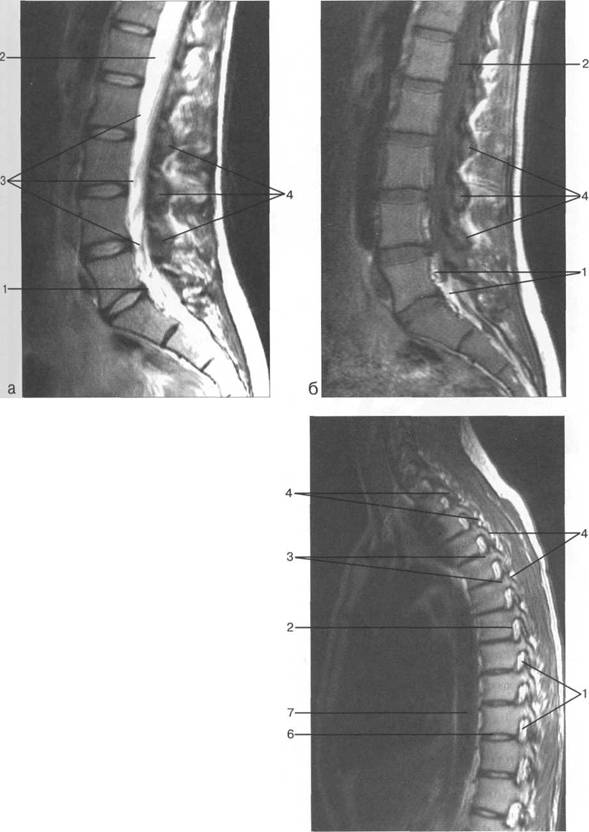

MPT. Cw_v.